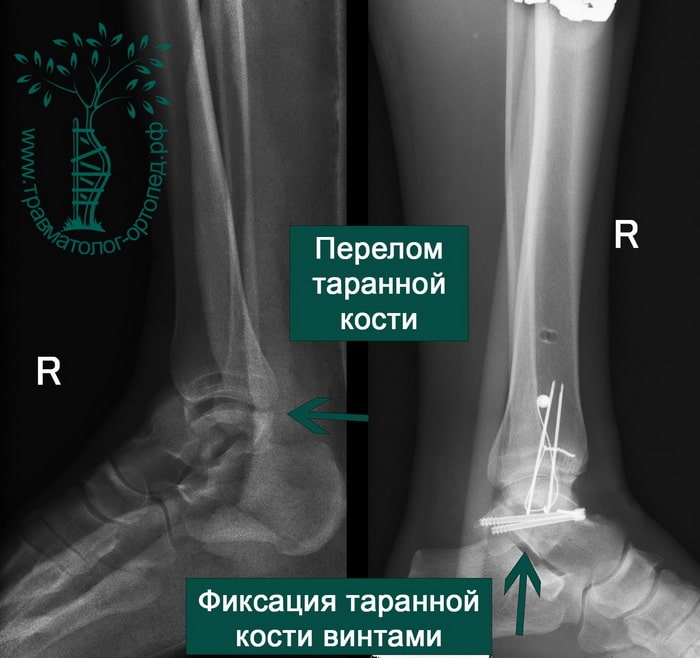

Переломы таранной кости

Переломы таранной кости — довольно редкое, но серьёзное повреждение, которое, как правило, связано с сильным ударом или падением. Они требуют тщательного лечения, поскольку могут привести к нарушению функции стопы и развитию остеоартрита.